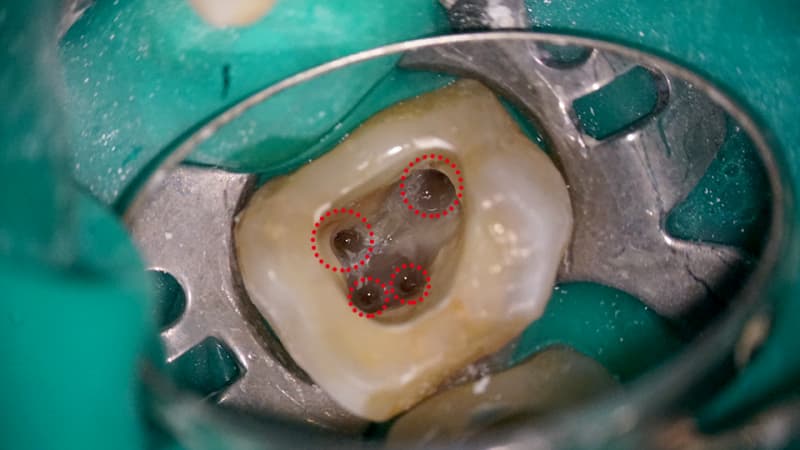

What's Visible Through the Microscope

Canal Access

Root Inflammation

Discovery

Crack Detection

Microscopic Treatment

We don't miss even the smallest details

invisible to the naked eye

Accurate diagnosis of cavities and tooth fractures

Precise treatment with up to 25x magnification

Minimize recurrence and side effects of treated teeth

Minimize damage to surrounding tissues with precise treatment

Dental microscopes, available only in select university hospitals and dental clinics, show even the smallest details invisible to the naked eye, enabling efficient preservation treatment of high difficulty.